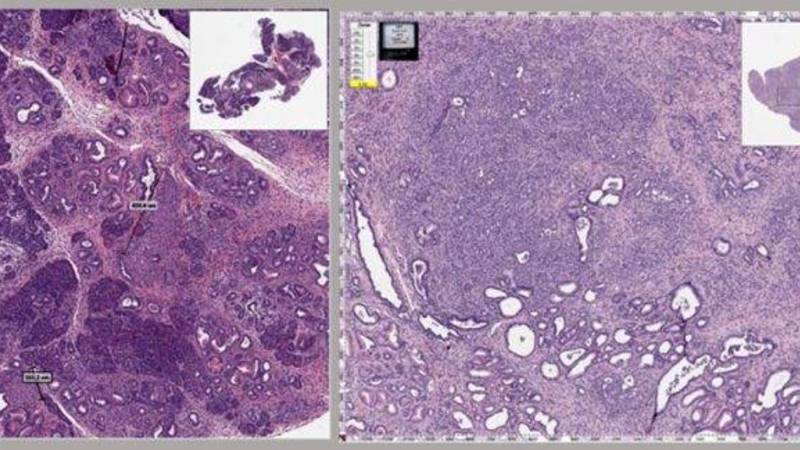

ويستخدم «الميبيندازول» في الأصل لمحاربة الديدان الأسطوانية والديدان الخطافية والالتهابات الطفيلية الأخرى في المعدة، عن طريق قطع إمداد الطفيليات بالتغذية، ومنع تكوين بروتين «التوبولين»، ما يؤدي إلى تجويع الطفيل حتى الموت. وأظهرت الدراسة أن «الميبيندازول» يعمل بشكل مشابه في سرطان البنكرياس عن طريق انهيار بنية الخلايا السرطانية، إلى جانب آليات أخرى مثل تقليل الالتهاب.